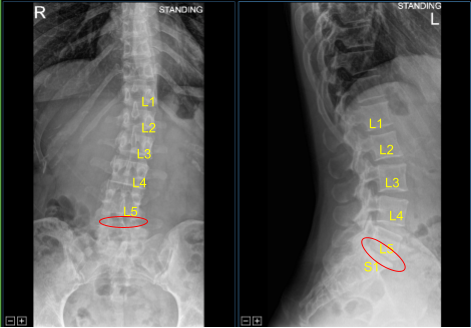

The patient presented to the neurosurgery clinic with signs and symptoms of lumbar spondylosis and radiculopathy at L5-S1 level of their lumbosacral spine. They failed extensive conservative measures and surgery is recommended to decompress and stabilize their lumbar spine.

Moderate Disc Degeneration